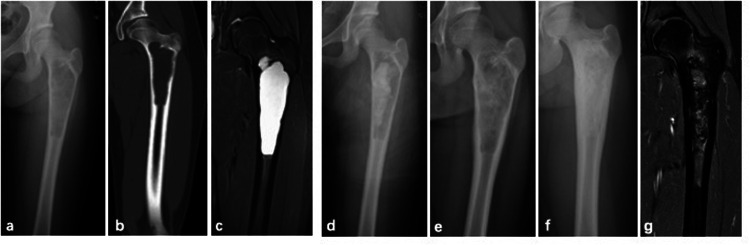

Methods: All patients underwent the PAIB procedure. Postoperative evaluation involved radiographic assessment to monitor recurrence and identify potential complications, with magnetic resonance imaging (MRI) performed when clinically indicated.

Results: In this cohort of 36 patients with SBC treated using the PAIB technique, the mean follow-up duration was 33.5 months (range: 12-66 months). Recurrence occurred in 6 patients (16.6%), including one case complicated by a pathological fracture. Five of the recurrent cases underwent repeat PAIB procedures, resulting in complete resolution in two patients. Postoperative imaging revealed small residual cysts in three cases. Bone healing was successfully achieved in 32 patients. Graft bone exudation, identified as a potential risk factor for recurrence, was observed in seven patients. All patients exhibited satisfactory functional outcomes throughout the follow-up period.

Abstract Image